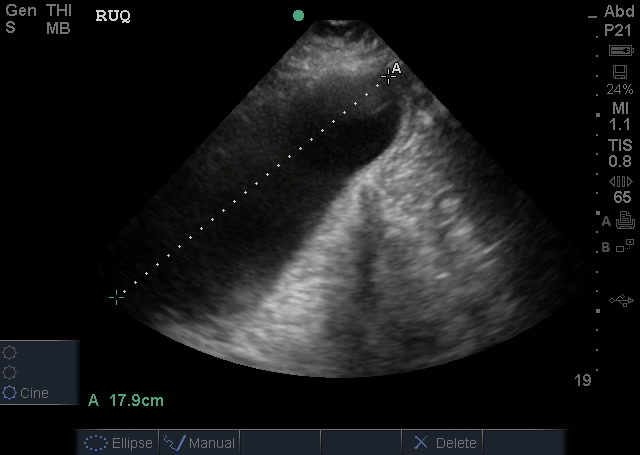

Gallbladder measurements:

The normal gallbladder measurements are an anterior gallbladder wall of 3mm, a width of 4cm and a length of no more than 9-10cm. The common bole duct (not measured) should be 6mm at the age of 60yrs (adding a mm for every decade above 60). The above image also shows a small amount of sludge but no obvious gallstone (it may have went into the bile duct and obstructed there). So, putting it together – this is obviously abnormal and evidence of acute cholecystitis.